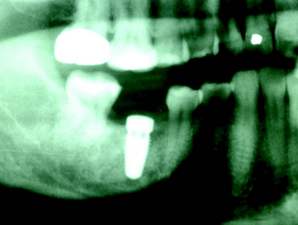

For dentists who are considering becoming involved with placing implants and for novice implantologists, some patients who are already missing teeth present with unpredictable implant sites and more difficult diagnoses (Is the maxillary sinus too close? Is there enough bone to place the implant above the inferior alveolar nerve? What happened to all of the attached gingiva? Is the bone wide enough to accept the implant?). This unpredictability is the main reason general dentists might shy away from learning to place implants and these are the same concerns of most new implantologists as they move ahead in their education.

As the primary dental care provider, the general dentist is perfectly positioned to not only make the diagnosis, but to educate and treat the patient to completion. Once the treatment has been accepted, the hopeless root (with no ferrule) is atraumatically extracted. If both the buccal and lingual walls remain intact, simple socket preservation techniques can be utilized so that in three to four months the general dentist now has “created” an optimal implant site. If pathology or less than traumatic extraction leaves you with a compromised buccal or lingual boney plate, then socket augmentation is performed, and an optimal implant site is available for implant placement in four to five months.